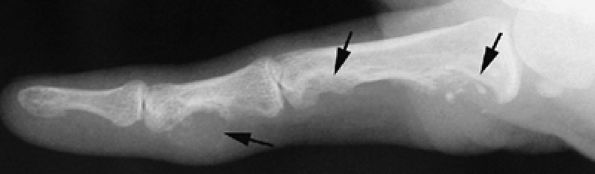

FIGURE 11.31 ● Mallet finger. (A) Fracture avulsion (arrow) of the base of the distal phalanx (lateral view). (B) Sagittal T1-weighted images in a different case showing a tear of the terminal band of the extensor apparatus (arrows) with thickening of soft tissues. There is bone edema (arrowhead) of the base of the distal phalanx without fracture.